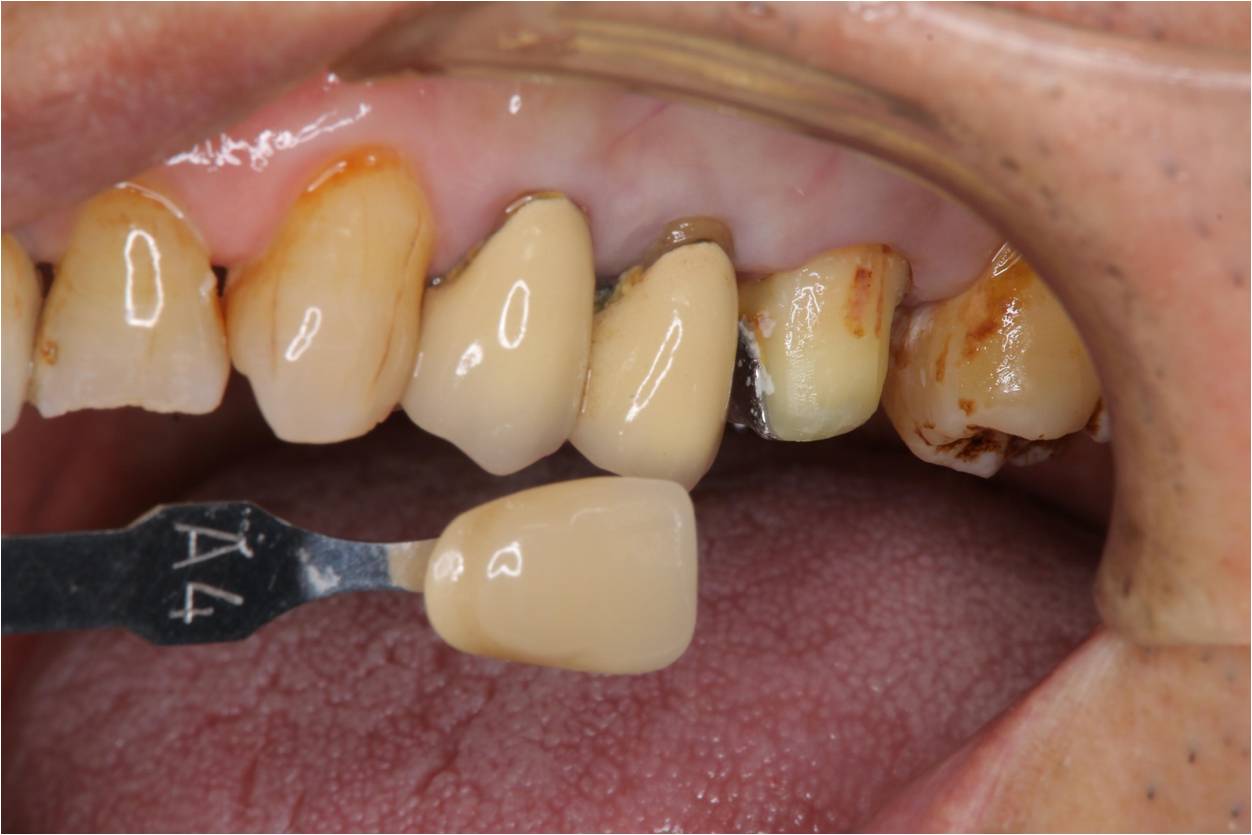

照相比色